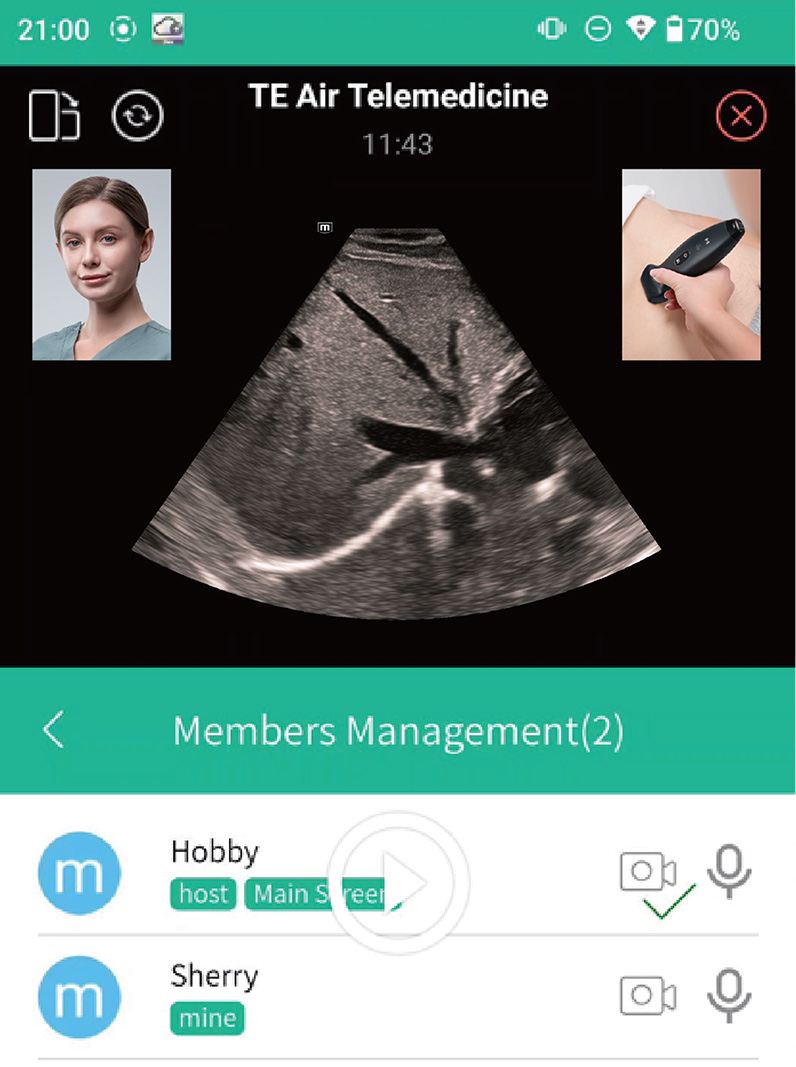

3Offre soluzioni per la gestione dei dati dei pazienti

4Completa il flusso di lavoro grazie alla perfetta interconnessione con il sistema informativo